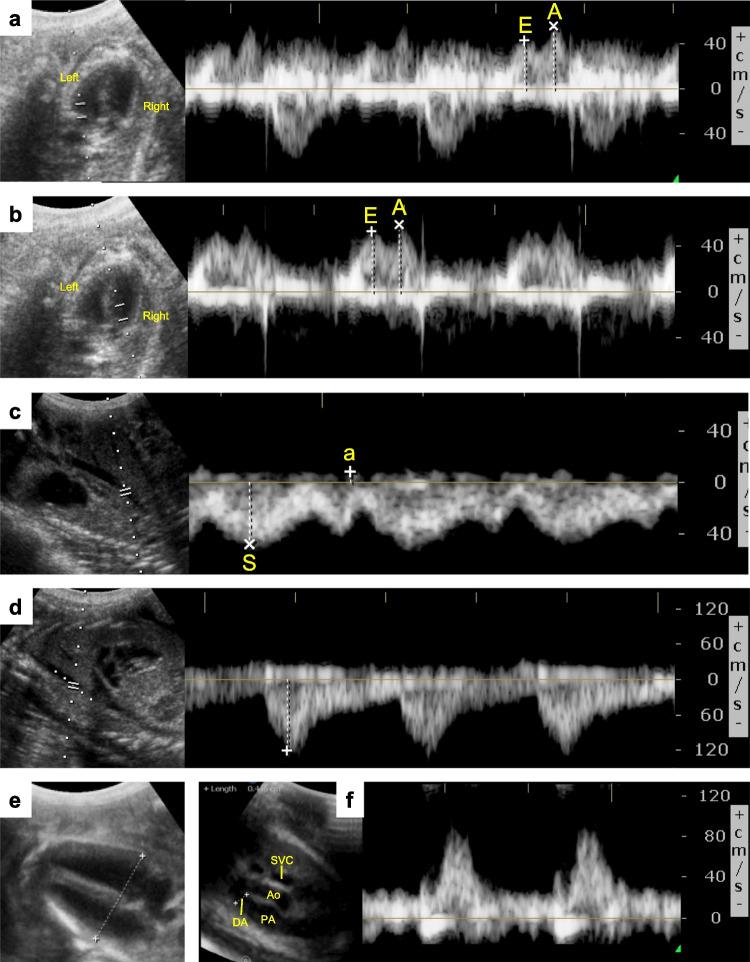

Despite widespread use, dosing regimens for antenatal corticosteroid (ACS) therapy are poorly unoptimized. ACS therapy exerts a programming effect on fetal development, which may be associated with an increased risk of cardiovascular disease. Having demonstrated that low-dose steroid therapy is an efficacious means of maturing the preterm lung, we hypothesized that a low-dose steroid exposure would exert fewer adverse functional and transcriptional changes on the fetal heart. We tested this hypothesis using low-dose steroid therapy (10 mg delivered to the ewe over 36 h via constant infusion) and compared cardiac effects with those of a higher dose treatment (30 mg delivered to the ewe over 24 h by intramuscular injection; simulating currently employed clinical ACS regimens). Fetal cardiac function was assessed by ultrasound on the day of ACS treatment initiation. Transcriptomic analyses were performed on fetal myocardial tissue. Relative to saline control, fetuses in the higher-dose clinical treatment group had significantly lower ratios between early diastolic ventricular filling and ventricular filling during atrial systole, and showed the differential expression of myocardial hypertrophy-associated transcripts including βMHC, GADD45γ, and PPARγ. The long-term implications of these changes remain unstudied. Irrespective, optimizing ACS dosing regimens to maximize respiratory benefit while minimizing adverse effects on key organ systems, such as the heart, offers a means of improving the acute and long-term outcomes associated with this important obstetric therapy.